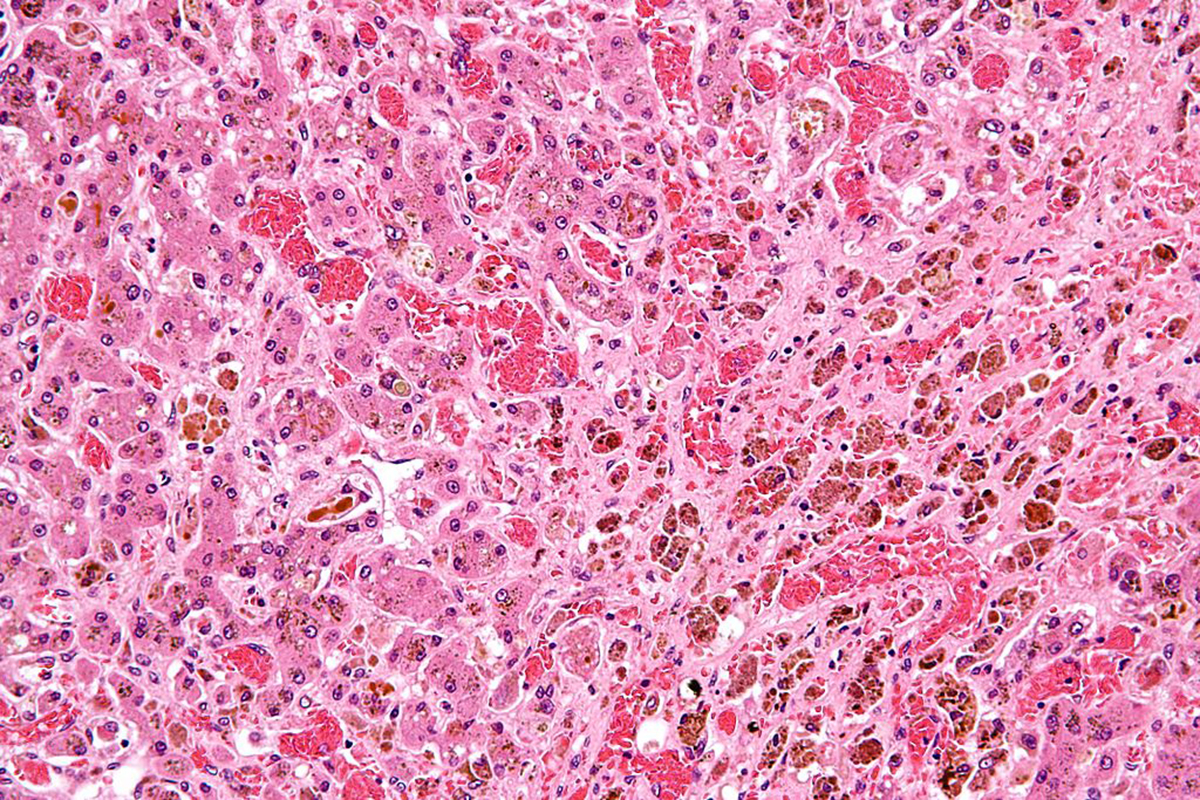

- Photo courtesy of Nephron by Wikimedia Commons : commons.wikimedia.org/wiki/File:Sickle_cell_disease_and_cirrhosis_-_high_mag.jpg